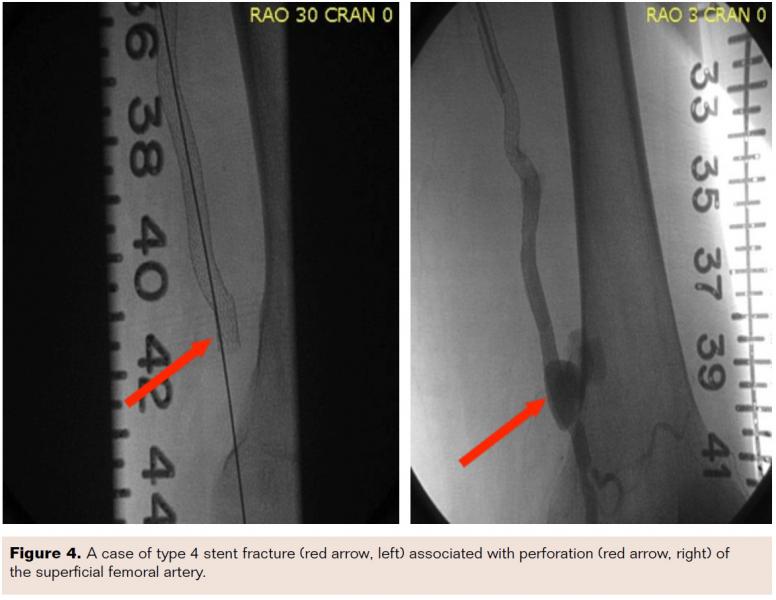

Of the 105 limbs with ISR, 31 limbs (29.5%) had angiographically confirmed SF. Of these 31 limbs, only 3 limbs had SF in the same anatomical segment as the ISR. In the remaining 102 limbs (90%), SF was not related to ISR. All three limbs with stent fracture associated ISR had type 3 fractures (Figure 1). The most common type of stenosis was diffuse in stent restenosis (Figure 2).

One of our patients who presented with ISR in the right SFA also had a previously implanted left SFA stent implanted 5 years prior. During angiography it was noted that the left SFA stent had a severe type 5 fracture with a pseudoaneurysm at the fracture site, with no associated restenosis or left leg symptoms (Figure 3). Another patient presented with severe thigh pain 24 hours after implantation of a nitinol self-expanding stent for prior total occlusion of the SFA. Fluoroscopy on presentation demonstrated a type 4 fracture and angiography demonstrated SFA perforation at the fracture site with active bleeding (Figure 4). This was successfully treated with a covered stent. These examples suggest that the severity and type of stent fracture may not always correlate with clinical presentation and symptoms.